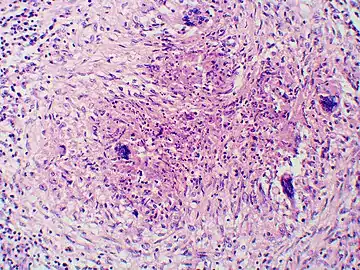

Large, broadly-based budding yeast cells characteristic of Blastomyces dermatitidis in a GMS-stained biopsy section from a human leg.

Inhaled conidia of Blastomyces are phagocytosed by neutrophils and macrophages in alveoli. Some of these escape phagocytosis and transform into yeast phase rapidly. Having thick walls, these are resistant to phagocytosis. Once they have transitioned to the yeast phase, the Blastomyces cells express the protein BAD-1, which helps the yeast cells attach to host cells, and also impairs activation of immune cells while inhibiting release of tumor necrosis factor. [23] In lung tissue, the cells multiply and may also disseminate through blood and lymphatics to other organs, including the skin, bone, genitourinary tract, and brain. The incubation period for pulmonary blastomycosis is 3 to 15 weeks, although 3050% of infections are asymptomatic.[24]

Once suspected, the diagnosis of blastomycosis can usually be confirmed by demonstration of the characteristic broad based budding organisms in sputum or tissues by KOH prep, cytology, or histology.[27] Tissue biopsy of skin or other organs may be required in order to diagnose extra-pulmonary disease. Blastomycosis is histologically associated with granulomatous nodules.